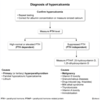

how are pregnant patients screened for hyperthyroidism? (3)

torn

TSH

(low TSH) ➜ [free T4]

(normal [free T4]) ➜ [Total T3]

use trimester-specific norms